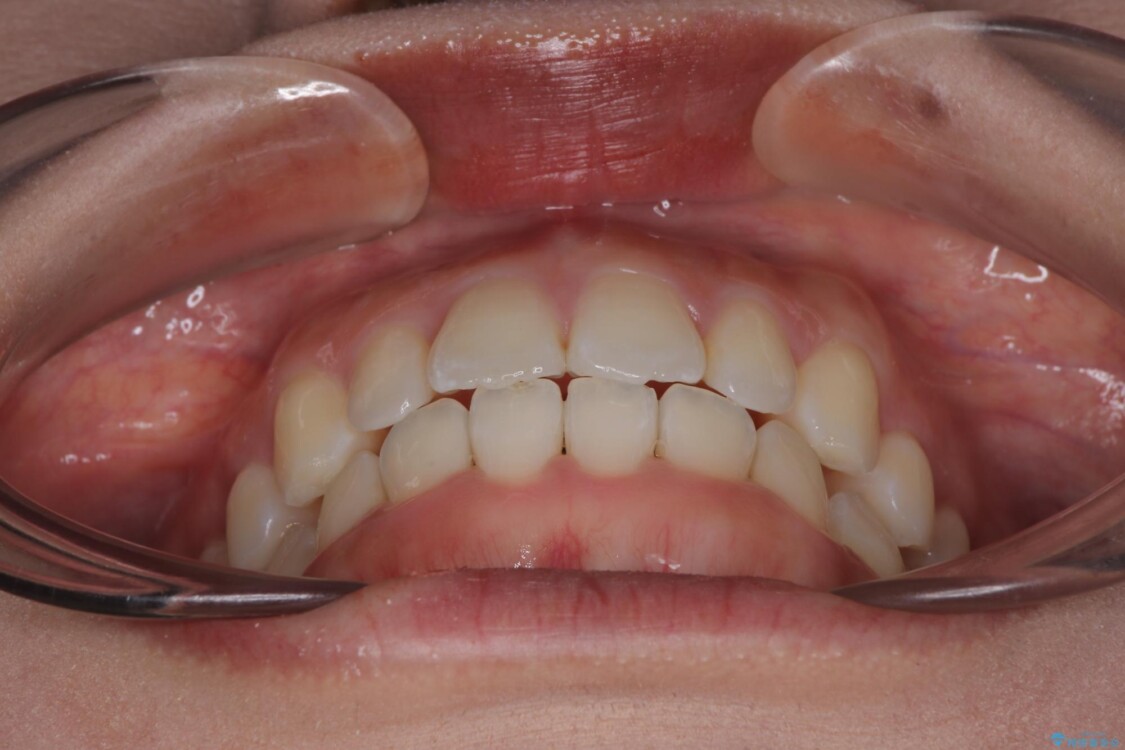

治療終了時

前歯が自然なアーチにきれいに並び、正中(上下の中心線)も整い、咬み合わせも良好です。

側方拡大することで、非抜歯であるにも関わらず前歯が前方に出ることなく、バランスの良い仕上がりとなりました。

「矯正装置が目立たず、思ったより短期間で仕上がりに満足しています。鏡を見るのが毎日楽しみになりました!」とうれしいお言葉をいただきました。

治療後

• 目立ちにくい表側装置で1年完了!狭いアーチを側方拡大し前歯のデコボコを整えた症例 治療後画像